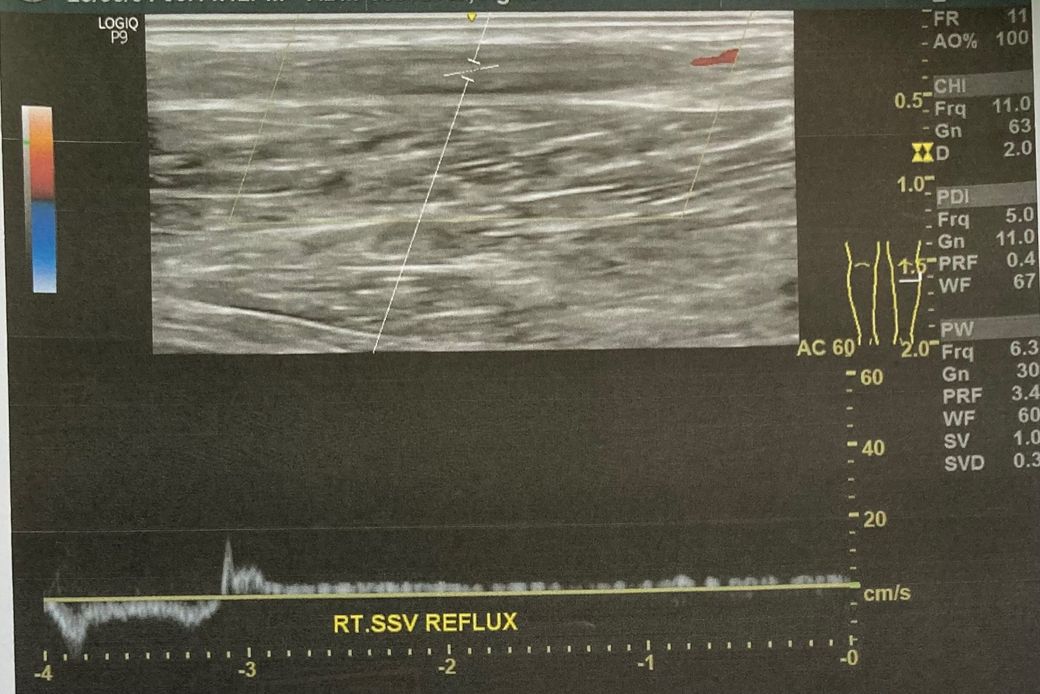

첨부하신 초음파 사진에서 RT. SSV REFLUX라는 표현이 보이는데, 이는 오른쪽 소복재정맥에 역류가 있다는 의미입니다.

정맥류에서 ‘역류’란, 혈액이 다리에서 심장 쪽으로 올라가지 못하고 다시 아래로 흘러 정체되는 상태를 말합니다.

일반적으로 0.5초 이상의 역류가 지속되면 비정상적인 역류로 간주하며, 그 정도가 심하면 수술적 치료 대상이 될 수 있습니다.

현재 SSV 역류가 명확히 확인되고 있으며, 이전보다 증상이 반복되고 있다면, 의료진이 수술을 권유한 것은 표준적인 판단으로 보입니다.